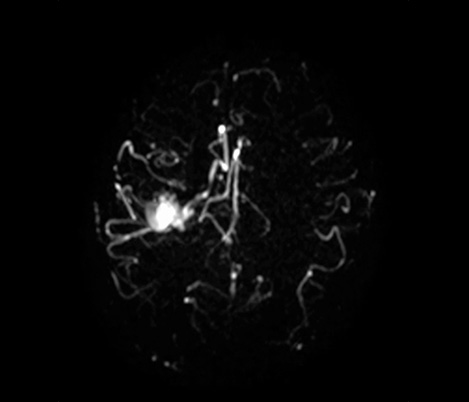

Klinische Fallbeispiele für nahezu jede anatomische Struktur Sehen Sie sich mehr als 100 klinische Fallbeispiele von Kollegen auf der ganzen Welt an, die zeigen, wie die digitale MR-Technologie von Philips Ihre Anforderungen in der Bildverarbeitung unterstützt.